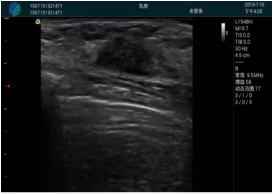

頸動(dòng)脈血流充盈飽滿,無外溢

肝內(nèi)血管顯示清晰,血流敏感無外溢

甲狀腺囊性結(jié)節(jié),囊壁鈣化,透聲好

甲狀腺囊性占位